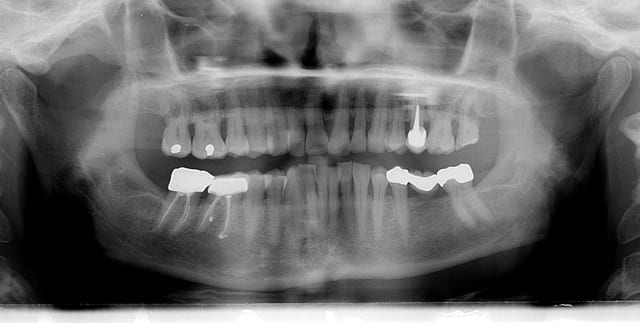

Au vu de la Pano.

ce cas présente

une alvéolyse horizontale (sous réserve de sondage)

pas de dents à intruser,

donc pas de risque de fabrication de poches avec accélération de destruction osseuse

avec environ 30% de perte osseuse dans le sens vertical, ce qui fait en surface radiculaire développée environ 50%

donc des dents facilement déplaçables

avec toutes ces réserves, on peut effectivement s’arrêter au 1°) des 5 étapes

Ton expertise parodontale est impressionnante, aussi je me permets de te soumettre ce cas qui pose problème.

Si une préparation parodontale était ici effectuée, penses-tu qu’il serait envisageable de faire un traitement ODF ?

Est-ce qu’il faudra alors prévoir du torque ?

Penses-tu qu’on puisse sauver certaines de ces dents ? Quelles avulsions faut-il d’emblée réaliser ?

Admettons donc que les problèmes infectieux de cet homme de 58 ans soient résolus (on peut toujours rêver, n’est-ce pas ?).

Au vu de ces :

« > destruction osseuse ancienne

> alvéolyse verticale et horizontale

> avec des poches infra-osseuses »,

- Penses-tu qu’il serait envisageable de faire un traitement ODF ?

- Est-ce qu’il faudrait alors prévoir du torque ?

- Sur quelle dent ?

58 ans, fumeur (cela se voit), adressé par son praticien traitant pour que je remettre « dans les clous » les dents qui ont migré, lui-même s’occupe du reste..

J’ai fait la pano le jour où je l’ai vu la première fois et commencé le traitement 2 mois et demi après.